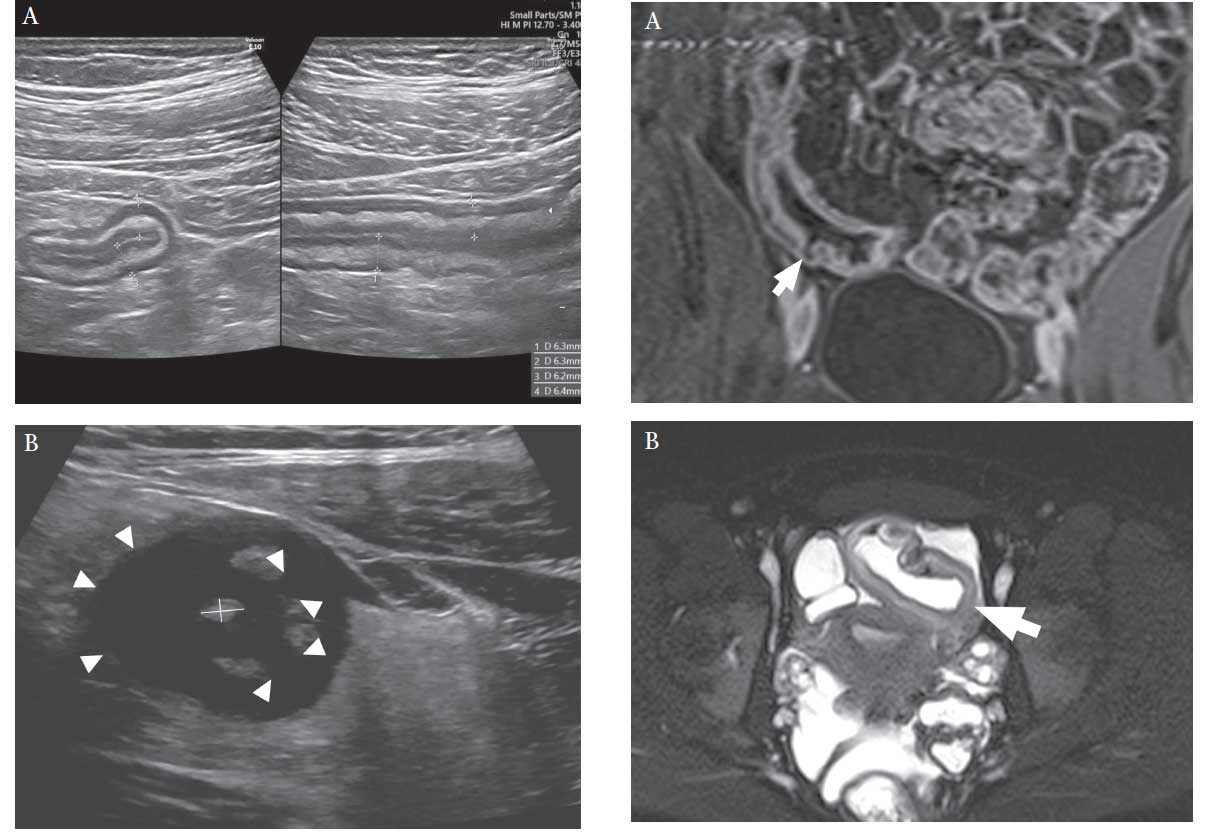

ARTIGO: ECCO-ESGAR Topical Review on Optimizing Reporting for Cross-Sectional Imaging in Inflammatory Bowel Disease